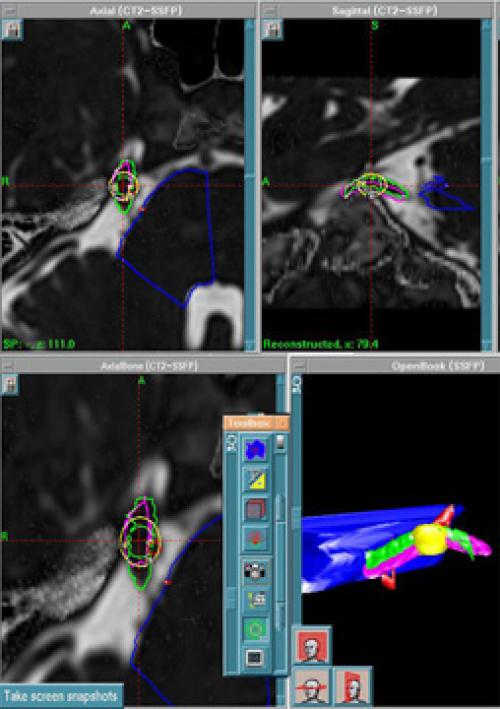

невралгии тройничного нерва с помощью Гамма-ножа применяется уже более 50 лет. Оно показано всем больным, у которых медикаментозная терапия не принесла эффекта после нескольких лет применения. Также лечение на Гамма-ноже показано больным, перенесшим микроваскулярную декомпрессию и другие хирургические манипуляции без положительной динамики. Целевой структурой при этом является корешок тройничного нерва, проходящий в ликворной цистерне после его выхода из ствола мозга. Эффективность операций и отдаленные результаты хорошо изучены и описаны литературе. Исчезновение болевого синдрома отмечается у 80-90% больных. Происходит это в сроки от несколько дней до нескольких месяцев после процедуры. Серьезных осложнений после лечения не бывает. Примерно у 7% пациентов может возникнуть временное онемение на лице.

Планирование радиохирургического лечения невралгии тройничного нерва.

Техника M. Hayashi, Tokyo Women's Medical University, Japan.

Преимуществами радиохирургии является высокая эффективность лечения при отсутствии осложнений, связанных с открытой хирургией (кровотечения, повреждение мозга, инфицирование, риск общей анестезии). Лечение занимает один день. Большинство пациентов возвращается к своей обычной активности на следующий день после операции.